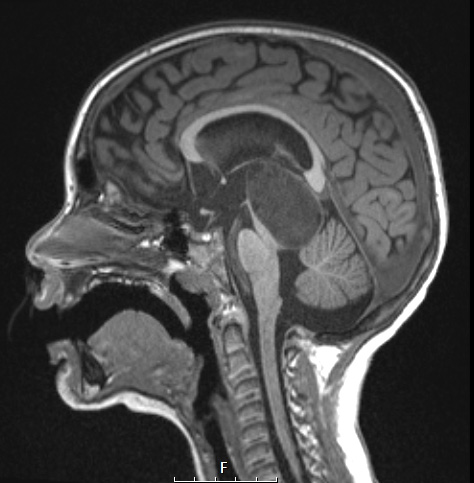

Washington University Experience | NEOPLASMS (GLIAL) | Angiocentric glioma | 8A3 Angiocentric glioma (Case 8) T1 MPRAGE NoC Sagittal

8A3,4 The tumor is hypointense in this T1-weighted scan (8A3) and fails to enhance with contrast (8A4).